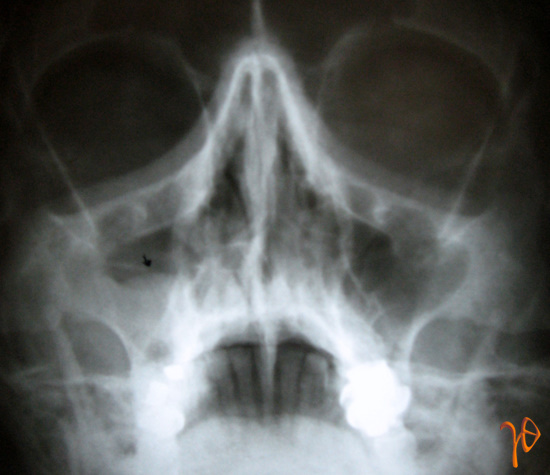

Στην πανοραμική ακτινογραφία δεν προέκυψαν ευρήματα από το οστούν της άνω γνάθου(Εικ.1). Στην απλή ακτινογραφία των ιγμορείων διαγνώστηκε συλλογή στο σύστοιχο ιγμόρειο(Εικ.2).

Εικόνα 2. Ακτινογραφία ιγμορείων με εικόνα συλλογής(βέλος-ΔΕ)